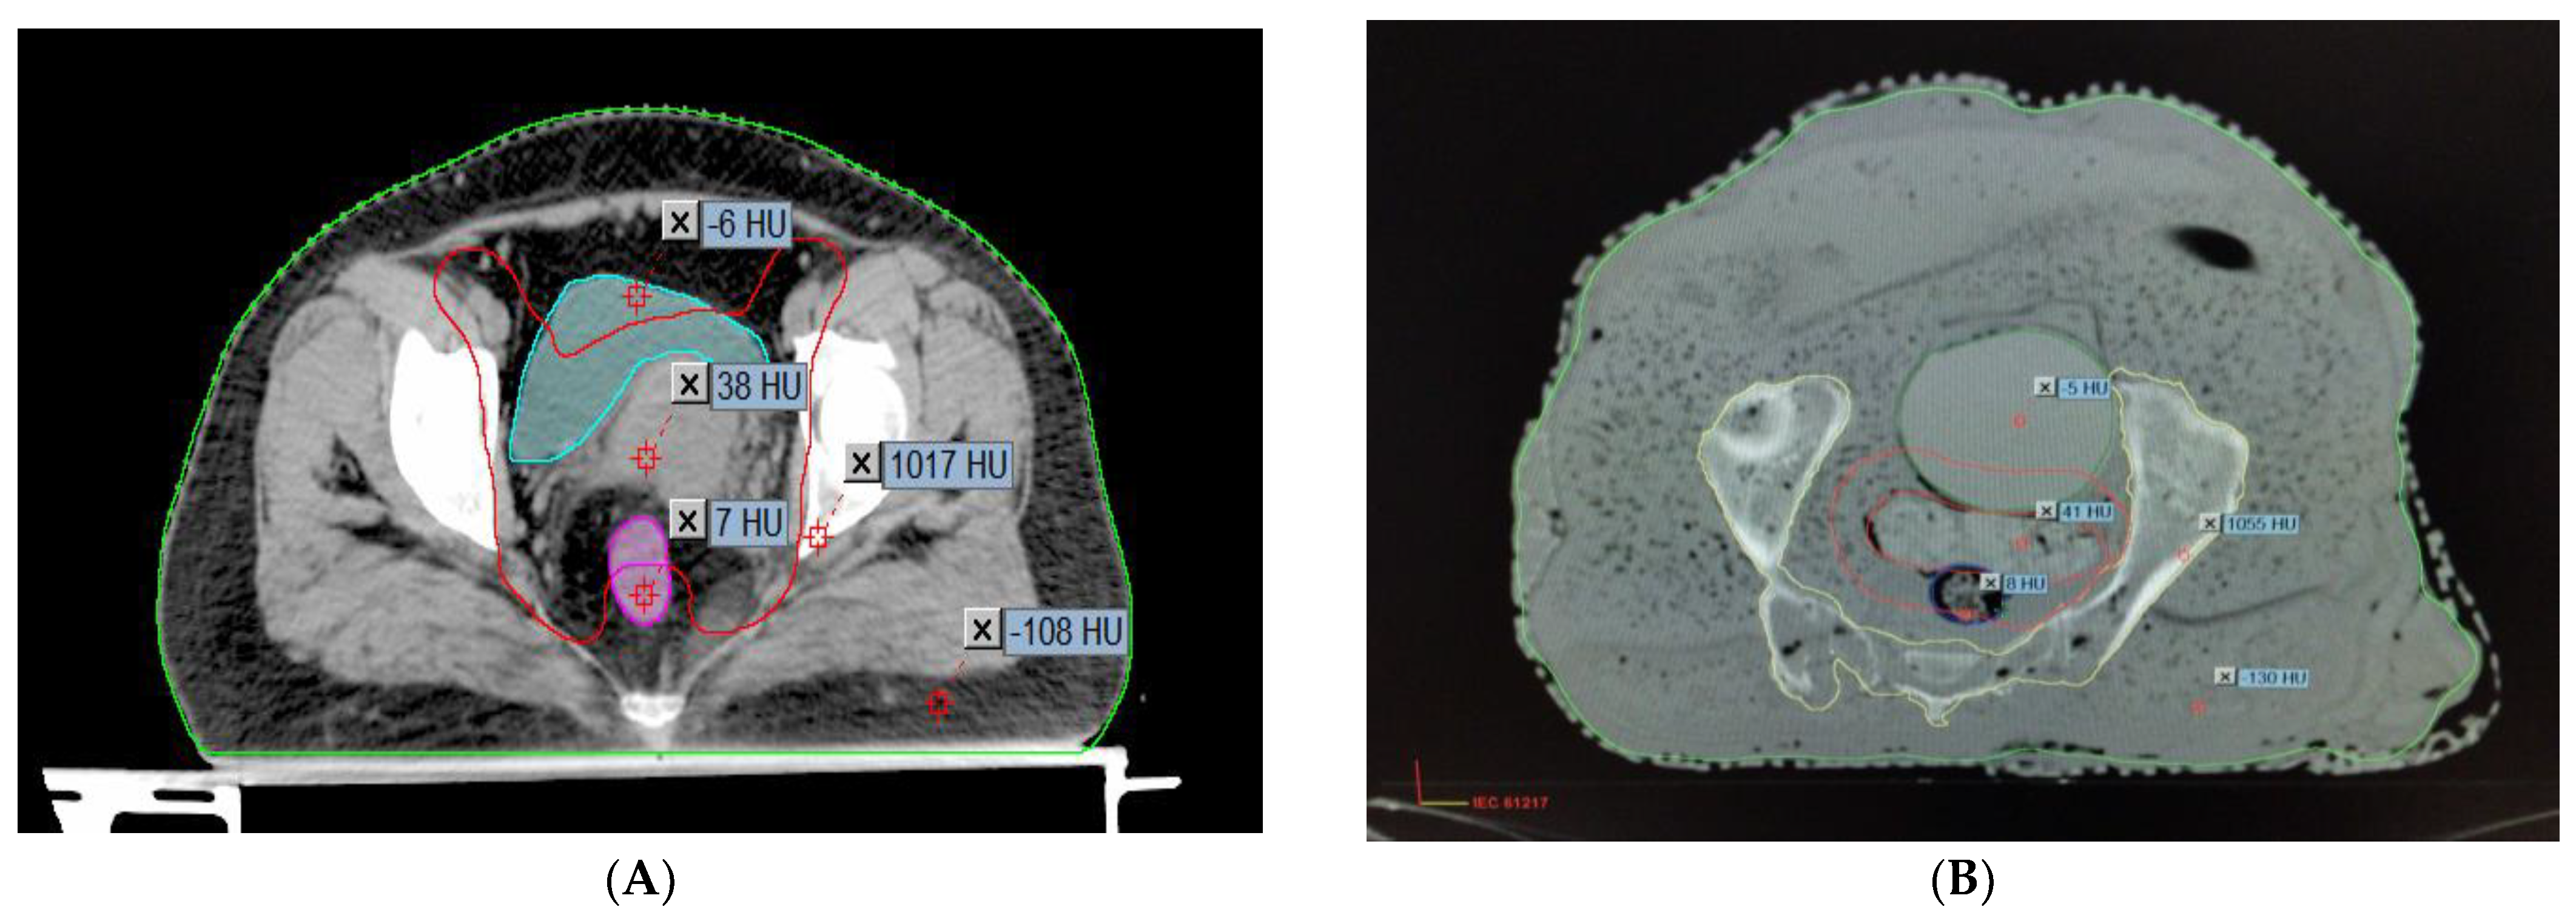

2.3. Comparison of the Hounsfield Units and the Relative Electron Densities of the Organs

2.4. Anatomical and Measuring Point Identification